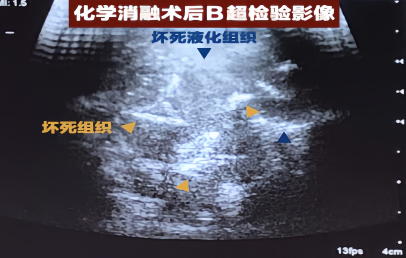

宠物肿瘤化学消融

宠物肿瘤化学消融评判治疗效果策略 综述